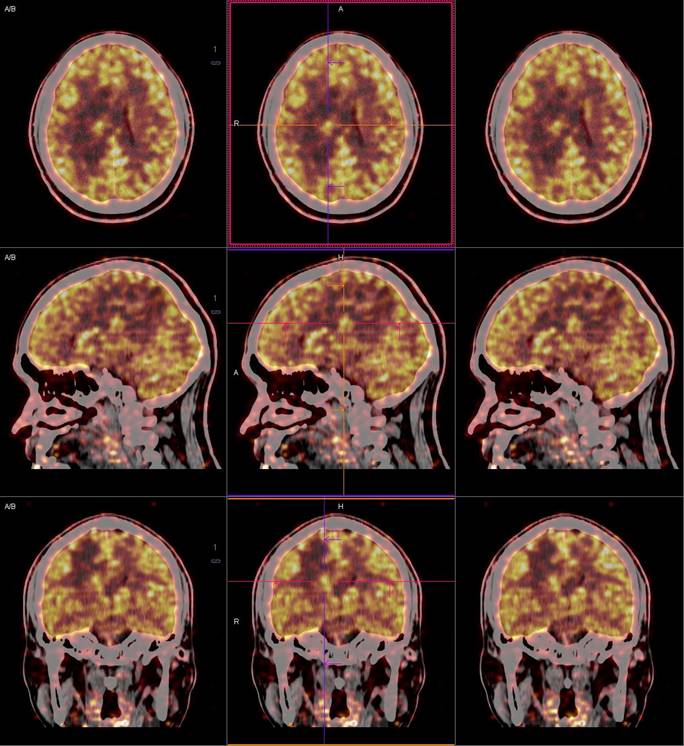

PET/CT影像圖

圖1

圖2

圖3

圖4

PET/CT檢查

影像診斷: 右側(cè)側(cè)腦室旁腦實(shí)質(zhì)內(nèi)結(jié)節(jié),代謝異常增高(SUVmax 12.13),伴瘤周水腫。

正電子發(fā)射計(jì)算機(jī)斷層(positron emission tomography,PET)是一種分子成像技術(shù),PET 應(yīng)用 18F-FDG等顯像劑可顯示人體內(nèi)細(xì)胞、分子或者基因水平的生物學(xué)、病理學(xué)過(guò)程,進(jìn)一步實(shí)現(xiàn)疾病早期定量與定性診斷。PET/CT使形態(tài)影像學(xué)與功能影像學(xué)得到了良好的結(jié)合,更有利于對(duì)腦膜瘤進(jìn)行全面的評(píng)價(jià)。既往研究發(fā)現(xiàn),18F-DG PET/CT對(duì)診斷WHOⅠ、Ⅱ級(jí)腦膜瘤具有較高的敏感度,F(xiàn)DG攝取可用于評(píng)估腦膜瘤的腫瘤增殖情況,以此達(dá)到鑒別腦膜瘤的良、惡性的目的。有學(xué)者統(tǒng)計(jì),WHOⅡ、Ⅲ級(jí)與 WHOⅠ級(jí)的平均標(biāo)準(zhǔn)化攝取值(standardized uptake value,SUV)分別為 2.51 (1.36,3.66)和 0.42 (0.12,0.73),WHOⅡ、Ⅲ級(jí)腫瘤與正常組織比率(T/N比率)存在差異,WHOⅡ級(jí)腦膜瘤的 SUVmax和最大T/N比率顯著高于 WHOⅠ級(jí)腦膜瘤。SUV和T/N比率對(duì)高級(jí)別腦膜瘤的診斷有較高的特異度。

此例,PET/CT全身檢查不僅排除了轉(zhuǎn)移瘤的可能性,增高的SUV值無(wú)創(chuàng)地鑒別腦膜瘤的良惡性,充分體檢PET/CT大視野、形態(tài)與功能影像結(jié)合的優(yōu)勢(shì)。